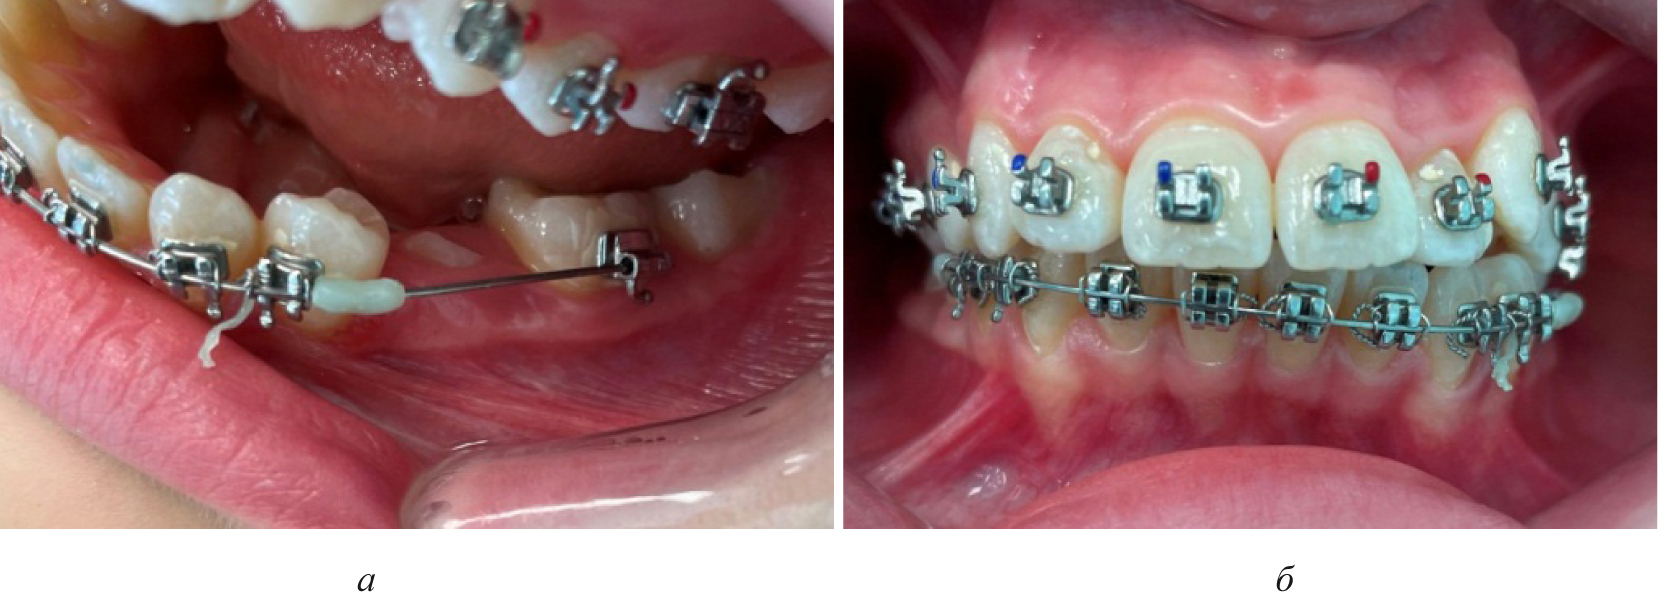

На первом этапе проводилось раскрытие пространства в области ретенированного зуба и создания условий для его прорезывания. После этого устанавливались элементы аппарата на противоположной челюсти (рис. 4).

Рис. 4. Создано место для прорезывания премоляра (а), установлена аппаратура на верхнюю челюсть (б)